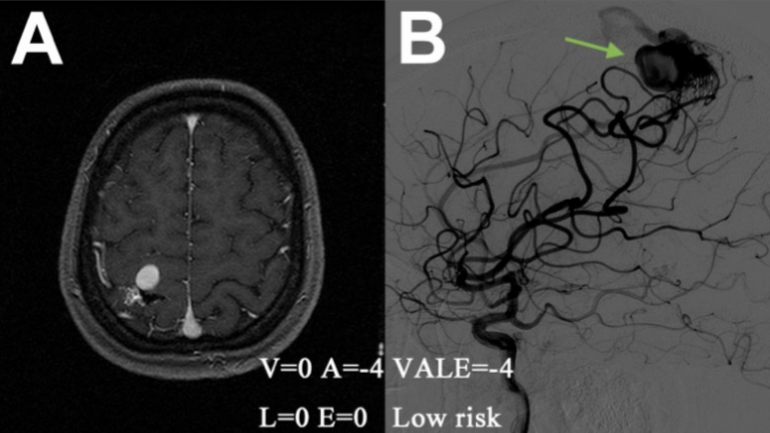

典型案例:A-B,1例伴有癫痫的未破裂AVM患者,通过VALE模型(脑室系统受累= 0,静脉瘤= -4,深部位置= 0,单一深静脉引流= 0,VALE= -4)评估为低危组,诊断后8.75年内随访无出血(静脉瘤:绿色箭头);

典型案例:C-D,1例以钝性头痛为表现的未破裂AVM患者,经VALE模型评定为中危组(脑室系统受累= 0,静脉瘤= 0,深部位置= 0,单一深静脉引流= 0,VALE= 0),诊断后随访6.25年无出血;